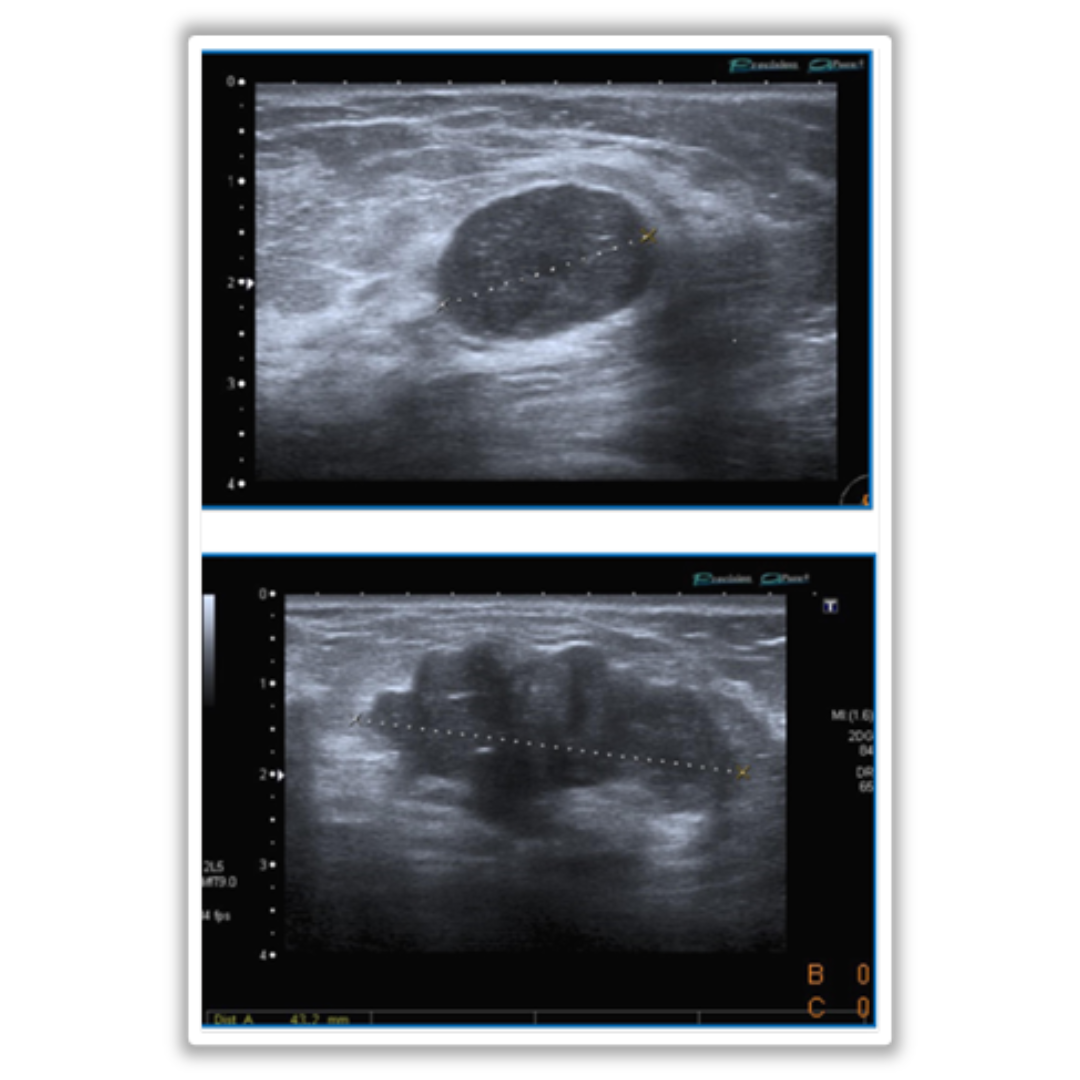

Imagen 6: B: distorsión de la arquitectura con espículas radiadas largas que confluyen centralmente. C: zona de distorsión de la arquitectura retroareolar.

Antes conocida como esclerosis papilar proliferativa, epiteliosis infiltrativa o lesión esclerosante encapsulada. Es una lesión proliferativa con fibroelastosis central y apariencia espiculada radiográfica e histológicamente.

• Al US: distorsión de la arquitectura sin nódulo asociado, ecoestructura heterogénea y sombra acústica posterior; si se detecta nódulo espiculado se asocia con mayor malignidad.

• DD: carcinoma invasor o intraductal, son lesiones que se clasifican como BI-RADS 4 por lo que se estudian mediante biopsia.